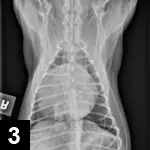

Hypovolemic or circulatory shock is the most common cause of shock seen in small animal practice. Hypovolemic shock results from a decreased intravascular volume, and causes commonly include hemorrhage, severe dehydration, and hypoproteinemia. Intraabdominal hemorrhage (Figure 1) may occur as a result of a ruptured splenic or hepatic mass, a coagulopathy, or trauma. Severe dehydration may be seen with prolonged fluid losses, as can be seen with vomiting and/or diarrhea.

An ultrasound image displays a transverse view of a canine abdomen, highlighting a fluid-filled structure near the liver. The measurement indicates a length of 2.48 cm, suggesting potential clinical significance for further evaluation.

Figure 1 Ultrasound image: peritoneal effusion and splenic mass